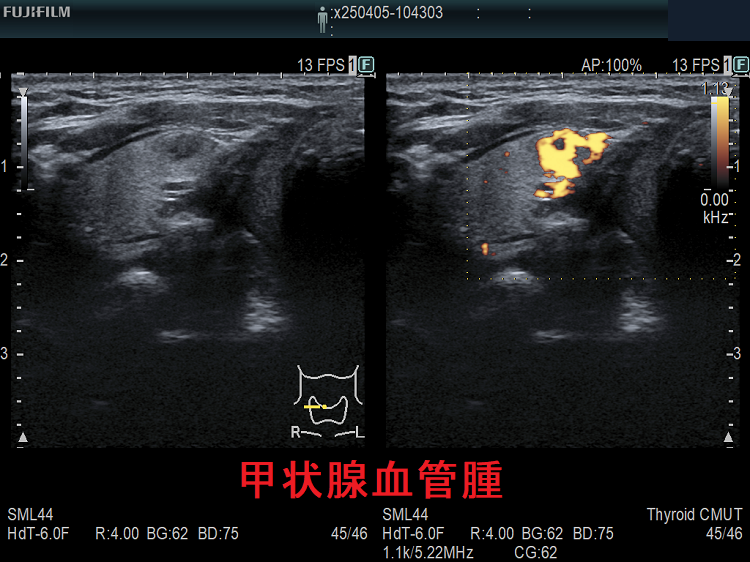

甲状腺に発生する血管腫は非常に稀で、日本の報告例もわずかです(日臨外会誌 72(3),579―583,2011)。

ケース①

ケース②

ケース③

甲状腺血管腫(拡大) ドプラーモード(eFlow);腫瘍内血管が3次元的に見え、毛玉の様。